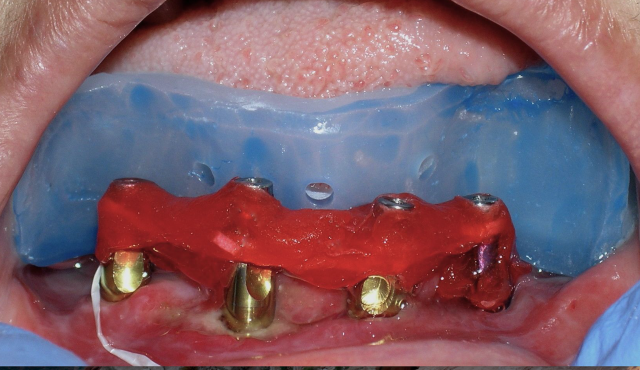

This patient had been managing with pemphigus vulgaris (PV) and as a result presented with advanced periodontal disease particularly evident in the lower arch, resulting in a hopeless prognosis. Minor trauma as a result of wearing a denture would certainly result in epithelial separation, acantholysis, or bullae (fluid-filled elevation greater than 1 cm in diameter) formation.

The restorative treatment plan included a mandibular fixed hybrid (fixed-detachable); however, the challenge in restoring this patient with PV is compounded by a limited ability to open her mouth. Traditionally, an open-tray final impression involves placing the implant-specific impression abutments and connecting with a rigid material such GC Pattern Resin LS (low shrinkage).

The challenge is how to insert an impression tray loaded with impression material up and over the impression abutments placed in the mouth. This can be painful or simply impossible in a scenario where the patient simply cannot open wide enough to accommodate, particularly with a time-sensitive material.

The final impression for the definitive restoration in this patient was completed with a sectional impression technique. The first component was made to capture the edentulous areas in the posterior segments of the mandibular arch, as well as the lingual aspect of the impression abutments. A visual evaluation can be completed to assure the appropriate capture of information prior to proceeding. The second component was made to capture the facial aspect of the impression abutments and to connect to the first component of the custom tray. The modified open-tray technique allowed for primarily an anterior path of removal after releasing impression abutments.